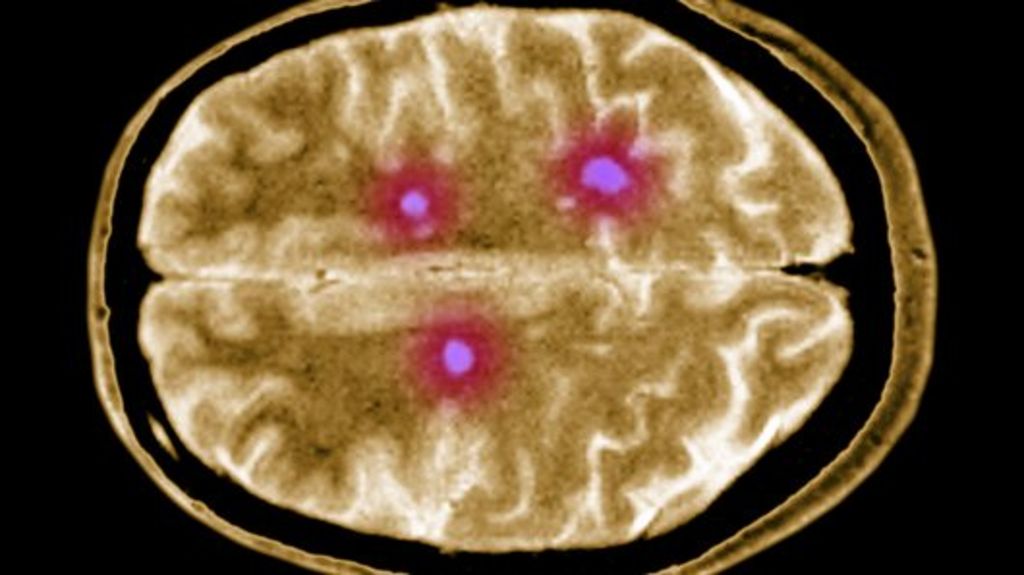

Multiple sclerosis is a chronic relapsing disease of the central nervous system, which is characterized by the formation of multiple scattered foci of demyelination in the brain and spinal cord.

A distinctive feature of this disease is the presence of foci of sclerosis scattered throughout the central nervous system without a specific localization – the replacement of normal nervous tissue with connective tissue.

- Multifocal lesion of the white matter of the brain.